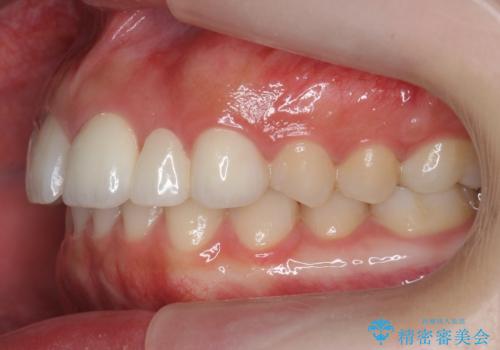

- 前歯の並びを主訴に来院。

前歯が出ており、また、左上の側切歯が1本生まれつき少ない状態でした。

また、右の奥歯の関係も上が前にある状態で大きくずれていました。

臼歯関係は無理に1級にしようとすると抜歯が必要になります。

今回は左右とも1歯対2歯の関係であるため、それは変えずに前歯を可及的にひっこめて足りない部分をブリッジで補う治療としました。

矯正後の前歯ブリッジについては横浜桜木町歯科の大元院長が担当しています。

奥歯の関係を完全に1級にするには右上の小臼歯の抜歯が必要でしたが、もともと左上の前歯が生まれつき少ないため今回は歯を抜かずに治療しています。